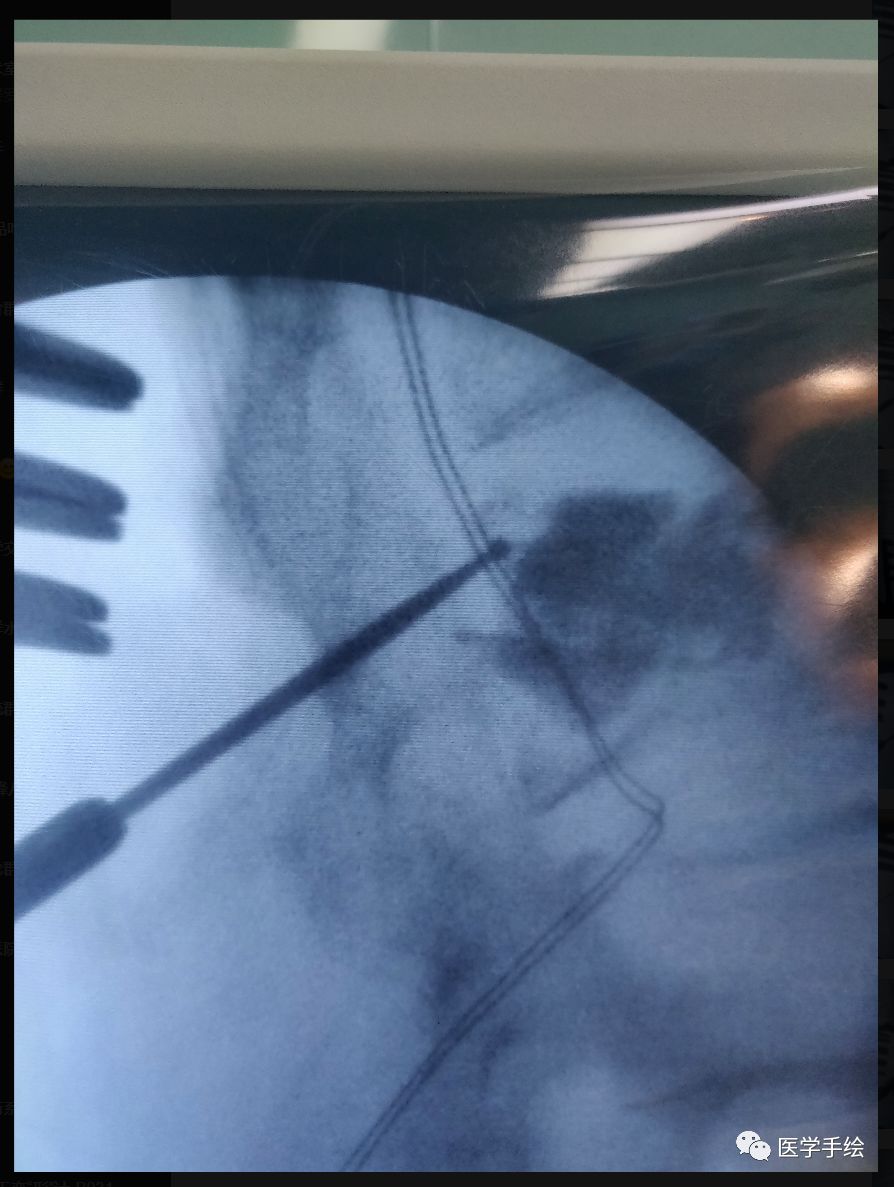

case:老年骨质疏松患者,既往L2行单侧(左侧)椎体成形手术。本次手术L2需要置入螺钉,左侧椎弓根螺钉由于骨水泥的存在置入困难,选择CBT螺钉。